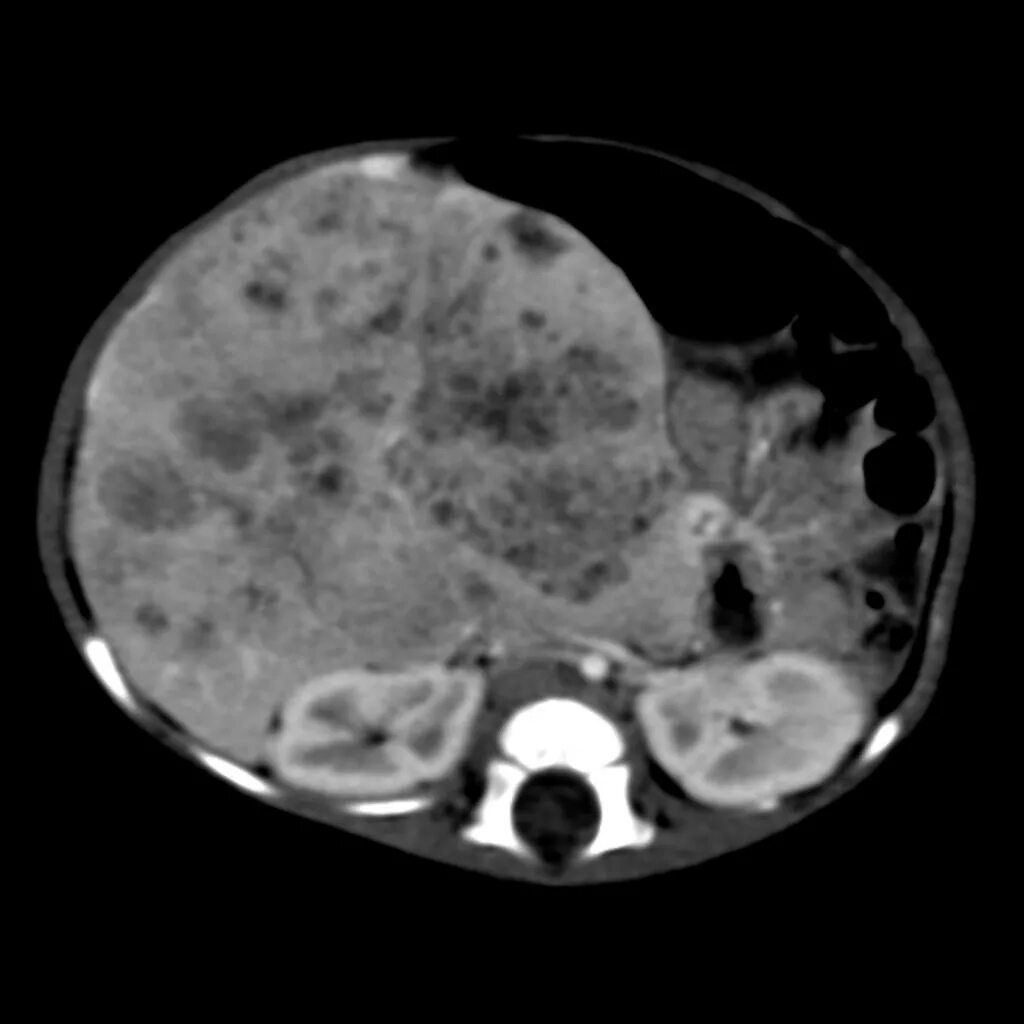

Бластома мозга